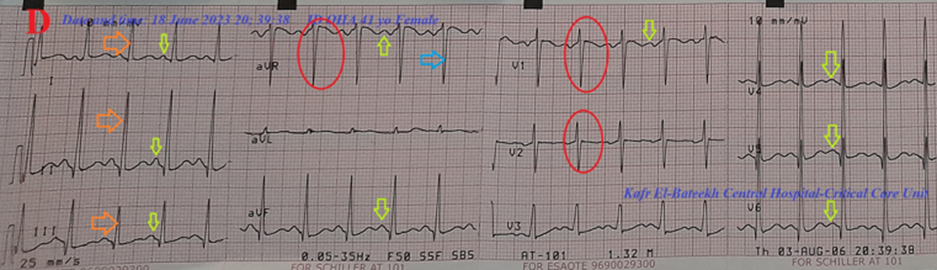

A 41-year-old married female housewife, patient, was presented to the intensive care unit (ICU) with palpitations, acute non-specific chest pain, and dizziness. Cough, headaches, and generalized body pain were associated symptoms. The patient has a history of diabetes mellitus 12 years ago, on long-acting insulin. She also has a history of bronchial asthma 20 years ago on intermittent anti-asthmatic medications. Upon general physical examination, the patient had tachypnea and distressed respiration, with a regular pulse rate (junctional tachycardia (JT) with VR of 165), blood pressure (BP) of 110/80 mmHg, respiratory rate of 25 bpm, a temperature of 36°C, and a pulse oximeter of oxygen (O2) saturation of 97%. No more relevant clinical data were noted during the clinical examination. The patient refused the referral for admission to the intensive care unit (ICU). He was initially managed at the ICU, with a junctional tachycardia, diabetes, non-specific chest pain, and Brugada syndrome. Initially, the patient was treated with O2 inhalation via an oxygen system line (100%, using a normal mask, 5L/min). The initial ECG tracing was performed on the initial presentation to the ICU, with one and a half calibration showing junctional tachycardia, normal axis, and coving-like ST-segment elevations in the aVR, V1, and V2 leads. There is a loose lead artifact in the V5 lead (Figure 1A). The second ECG tracing was taken within 3 minutes of the above ECG tracing, with one and a half calibration showing junctional tachycardia, interlacing of premature junctional complexes in V1 and V2 leads, with the same changes as above. But with AC artifacts and Wavy triple sign (Yasser's sign) in V6 lead (Figure 1B). The patient was treated with amiodarone IV bolus (300 mg IV over 20 minutes, then a continuous IVI at a rate of 1 mg/min for 6 hours). The patient was monitored hourly for vital signs and O2 saturation. The third ECG tracing was taken within 22 hours of the above ECG tracing, with one and a half calibration showing sinusoidal AF, normal axis, and disappearance of the above coving-like ST-segment elevations (Figure 1C). Amiodarone IV was given as a maintained dose, Diltiazem tablets (60mg, OD), SC Enoxaparin 40 mg, OD, and Warfarin tablet (5 mg, OD) were added. There is a new mild fever (temp of 38.5°C), tachypnea, dry cough, and frequent micturition. Urine analysis on the second day of ICU admission showed: pus over 50, RBCs: 10-12, and epithelial cells (++). The fourth ECG tracing was taken within 42 hours of the above ECG tracing, showing sinus tachycardia, normal axis, a coving-like ST-segment elevations in the aVR, V1, and V2 leads (Figure 1D). The fifth ECG tracing was taken within 6 hours of the above ECG tracing, showing sinus tachycardia, right axis deviation, with coving-like ST-segment elevations in I and aVL leads. There is a loose lead artifact in V2 lead (Figure 1E). Cefotaxime vials (1 gm IV BID) and paracetamol (500 mg TID as needed) were added. The sixth ECG tracing was taken within 1 minute of the above ECG tracing, showing sinusoidal AF, right axis deviation, with coving-like ST-segment elevations in the I and aVL leads. There is a loose lead artifact in V2 lead (Figure 1F). The seventh ECG tracing was taken within 1 minute of the above ECG tracing, showing sinusoidal AF, right axis deviation, with coving-like ST-segment elevations in I and aVL leads. There is a loose lead artifact in the V2 lead (Figure 1G). The eighth ECG tracing was taken within 24 hours of the above ECG tracing, showing sinusoidal AF, right axis deviation, with coving-like ST-segment elevations in the I and aVL leads. There is sagged ST-segment depression in the V4-6 leads (Figure 1H). The ninth ECG tracing was taken within 7 hours of the above ECG tracing, showing sinusoidal AF with normal axis (Figure 1I). The tenth ECG tracing was taken within 5 days of the above ECG tracing, with one and a half calibrations, showing junctional tachycardia, left axis deviation, with coving-like ST-segment elevations in the III, aVR, and V1 leads. There is a retrograde P wave in V6 lead (Figure 1J). The eleventh ECG tracing was taken within 8 hours of the above ECG tracing, showing sinusoidal AF, right axis deviation, with coving-like ST-segment elevations in I and aVL leads. There is equivocal QRS in the aVR lead (Figure 1K). The chest X-ray film PA view performed on the initial presentation to the ICU shows tail-like outward apical elongation. There are mild right and left consolidation opacities (Figure 2A). The plain film of chest CT performed on the initial presentation to the ICU showed tail-like outward apical elongation with a narrow lower black recess separating the left diaphragmatic surface and lower surface of the right heart (Figure 2B). Serial cuts of chest CT were done on the initial presentation to the ICU, showing no abnormalities (Figure 2C). Serial cuts of brain CT were done on the initial presentation to the ICU, showing no abnormalities (Figure 2D). The echocardiography was done within 4 days after the ICU presentation, showing tachycardia, mild mitral regurgitation, and a good LV systolic function of an EF of 53% (Figure 3). The initial laboratory: complete blood count (CBC); Hb was 11.3 g/dl, RBCs; 5.37*103/mm3, WBCs; 12.0*103/mm3 (Neutrophils; 53.7 %, Lymphocytes: 36.1%, Monocytes; 8.2%, Eosinophils; 0% and Basophils 0%), Platelets; 327*103/mm3. CRP was 6.0. SGPT was (26.7 U/L). Serum albumen was 4.2 gm/dl. Serum creatinine was (0.97 mg/dl). RBS was (254 mg/dl). D-dimer was 0.3ug/ml. ABG was done in the third day; (PH; 7.41, PCO2; 49.6 mmHg, HCO3; 31.8 mmHg, So2; 96%, and PaO2; 78 mmHg). INR was 1.04 with a prothrombin time of 13.08 seconds. The associated electrolytes in the ABG profile: Plasma sodium was 160 mmol/L. Serum potassium was (3.2 mmol/L). Serum ionized calcium was (1.01 mmol/L). The CBC was repeated in the third day; Hb was 11.2 g/dl, RBCs; 5.33*103/mm3, WBCs; 13.7*103/mm3 (Neutrophils; 67.6 %, Lymphocytes: 27.6%, Monocytes; 4.8%, Eosinophils; 0% and Basophils 0%), Platelets; 322*103/mm3. The troponin initial test was negative. On the ninth day; The CBC: Hb was 10.8 g/dl, RBCs; 5.17*103/mm3, WBCs; 13.8*103/mm3 (Neutrophils; 63.7 %, Lymphocytes: 31.4%, Monocytes; 4.9%, Eosinophils; 0% and Basophils 0%), Platelets; 210*103/mm3. CRP was 12.0. SGPT was (31.0 U/L). Serum creatinine was (0.6 mg/dl). Rheumatoid factor was negative. Migratory Brugada syndrome, variable interlacing arrhythmias, ECG axis deviations, and mild chest and urinary tract infections in a diabetic patient are the most probable diagnosis. Within eleven days of the above at-ICU management, the patient finally showed nearly complete clinical and ECG improvement. The patient was continued on Diltiazem tablets (60 mg, OD), Amiodarone tablets (200 mg, OD), Warfarin (5mg, OD), long-acting insulin, oral calcium, and Vitamin-D preparations for 14 days with further recommended cardiac and urological follow-up.

Figure 1: Serial ECG tracings; A. tracing was done on the initial presentation to the ICU with one and a half calibration, showing junctional tachycardia (of VR 165), normal axis (golden arrows), with coving-like ST-segment elevations in the aVR, V1, and V2 leads (red circles). There is a loose lead artifact in V5 lead (large grey arrow).

Figure 1B: tracing was taken within 3 minutes of the above ECG tracing with one and a half calibrations, showing junctional tachycardia (of VR 159), interlacing of premature junctional complexes in V1 and V2 leads, with the same changes. But with AC artifacts (orange arrows) and Wavy triple sign (Yasser's sign) in V6 lead (light blue arrow).

Figure 1C: tracing was taken within 22 hours of the above ECG tracing, with one and a half calibrations, showing sinusoidal AF (of VR 117; lime arrows and golden circles), normal axis (orange and light blue arrows), and disappearance of the above coving-like ST-segment elevations.

Figure 1D: tracing was taken within 42 hours of the above ECG tracing, showing sinus tachycardia (of VR 123; lime arrows), normal axis (golden arrows and light blue arrows), with coving-like ST-segment elevations in aVR, V1, and V2 leads (red circles).

Overview: A middle-aged married female housewife, patient, was presented to the ICU with junctional tachycardia, diabetes, non-specific chest pain, Brugada syndrome, and past bronchial asthma. The primary objective for my case study was the presence of a middle-aged married female housewife, patient, with junctional tachycardia, diabetes, non-specific chest pain, Brugada syndrome, and past bronchial asthma in the ICU. The secondary objective for my case study was the question of how to manage the case. Mild chest and urinary tract infections were associated with the condition (Figures 2A-2B). There were variable associated arrhythmias throughout the course of the ICU admission. It started with junctional tachycardia (Figures 1A-1B), then sinusoidal AF (Figure 1C), then sinus tachycardia (Figures 1D-1E), then sinusoidal AF (Figures 1F-1I), then junctional tachycardia (Figures 1J-1K). There were also different serial changes in axis deviations in the ECG in the course of the ICU admission. It started with normal axis (Figures 1A-1D), then right axis deviation (Figures 1E-1H), then normal axis (Figure 1I), then left axis deviation (Figure 1J), then right axis deviation (Figure 1K). Indeed, although there is no clear known cause for these different serial changes in axis deviations in the ECG, Amiodarone is suggested as the cause [17]. Naranjo's probability scale was used to assess the probable relationship between these different serial changes in axis deviations and the causative agent, Amiodarone. Naranjo's probability scale in the current case study was +8. It means that there was a probable relationship between the serial changes in axis deviations and the causative Amiodarone (Table 1).

There were also variable and changeable topical changes in coving-like ST-segment elevations of Brugada syndrome in the ECG in the course of the ICU admission. It started with coving-like ST-segment elevations in aVR, V1, and V2 leads (Figures 1A-1D), then coving-like ST-segment elevations in I and aVL leads (Figures 1E-1H), then the normal ST-segment in all the

above leads (Figure 1I), then coving-like ST-segment elevations in III, aVR, and V1 leads (Figure 1J), then coving-like ST-segment elevations in I and aVL leads (Figure 1K). These transitions in coving-like ST-segment elevations from one specific lead to another specific lead are a new description regarding Brugada syndrome. So, it is named as "Yasser's migration sign" (Figure 4).